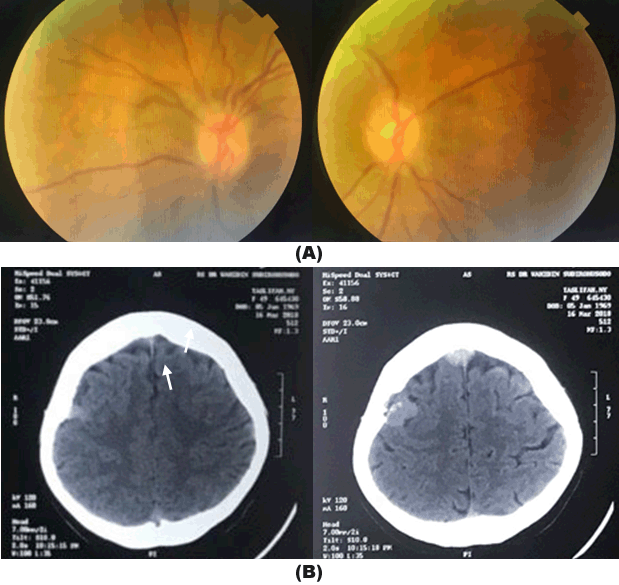

A 49-year-old woman with breast carcinoma was referred from oncology with double vision on left gaze in the last two weeks. She was diagnosed as having breast carcinoma since two years ago and was treated with chemo-radiation therapy and hormonal therapy. She complained headache, fever and severe vomiting. History of head trauma and decrease of visual acuity were denied. Ophthalmic examination showed best corrected visual acuity were 20/25 in both eyes, anterior segment was within normal limits. There was restriction in abduction on left eye corresponding to abducens nerve palsy (Figure 1). Posterior segments (funduscopy) of both eyes were normal (Figure 2A). We diagnosed her with left abducens nerve palsy. Non-contrast head Computed Tomography (CT) scan on axial slice showed hyperdense lesion with irregular firm edges, sized 2x1cm in the right frontal lobe and 2x2,4cm in the right parietal lobe. The lesion spreads and destructs the right frontal and parietal bones. CTScan result suggested intracranial and bone metastasis (Figure 2B).

A 41-year-old woman with cervix carcinoma was referred from Gynaecology department with sudden decrease of vision and family noticed she had a squint from last three days. She complained a severe headache and vomiting. There was history of chemotherapy for two cycles and was discontinued about two years ago. Visual acuities were hand movement on both eyes, there was limitation of abduction on right eye (Figure 3). Anterior segments was normal. Funduscopy showed papilledema on both eyes (Figure 4). Head Multiple Slice Computed Tomography (MSCT) scan with contrast on axial slice showed heterogenous lesion and enhanced with contrast with irregular solid, firm edges, sized 4.2x5.8x4 cm, with focal edema around which pushed and narrowed the left lateral ventricle, which caused midline shift 0.5 cm to the right in parietooccipital lobe sinistra suggesting anaplastic astrocytoma (Figure 5).

Figure 2: (A) Funduscopy photographs of the patient showed normal posterior segments on both eyes. (B) Hyperdense lesion with irregular firm edges, sized 2x1cm in the right frontal lobe and 2x2.4 cm in the right parietal lobe (arrow).

Figure 5: Multiple slice computed tomography scan with contrast showed parietooccipital lobes mass, suggestive of anaplastic astrocystoma (arrow).